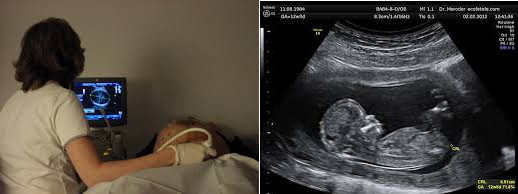

Estímulo

- Información sobre los ultrasonidos en su uso

en las ecografías de una mujer embarazada.

- Aleatoriedad:

Se presenta una imagen seleccionada al azar, de entre tres posibles.

Las tres imágenes aparecen una por cada pregunta, siguiendo un ciclo

aleatorio.